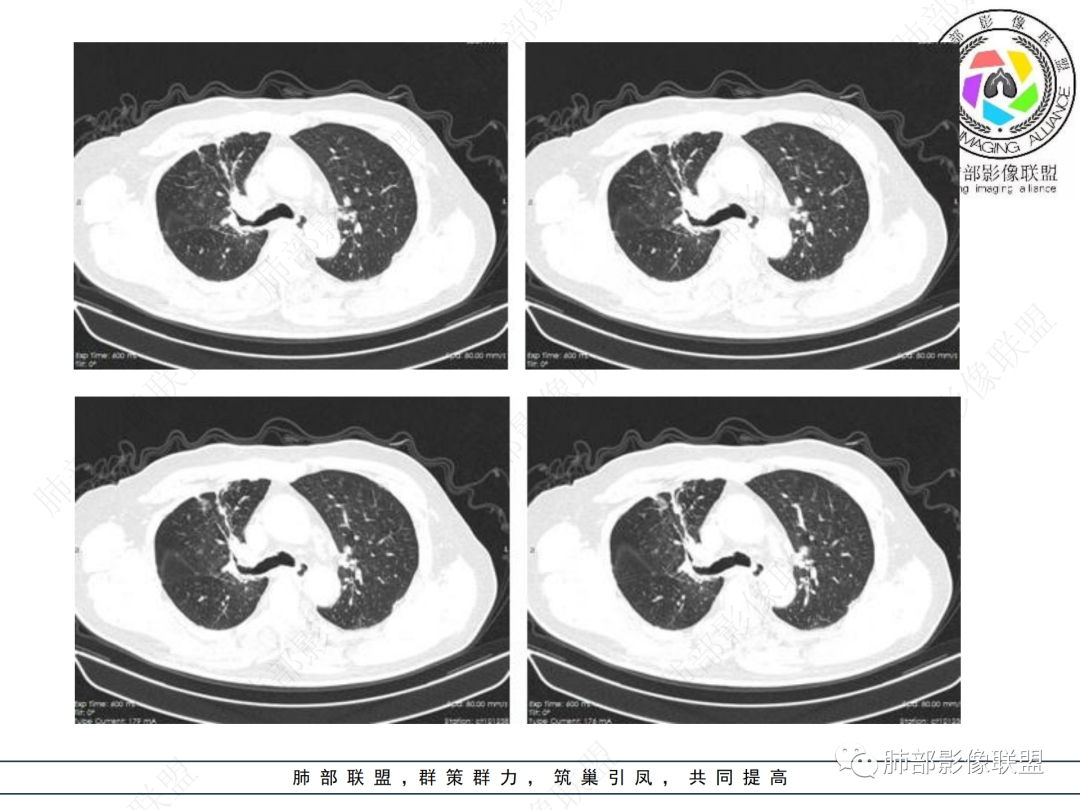

右肺上叶可见一团块影,边界清,有膨隆有凹陷,边缘可见毛刺,斜裂可见牵拉,不均匀强化,内可见液化,临近支气管未见明确阻塞,考虑腺癌可能,鉴别脓肿,结核等

右肺上叶团块,边缘毛糙,长索条,周围斑点影,邻近胸膜增厚,不均匀强化,其内小低密度灶边界清,考虑炎性肉芽肿,腺癌待排

右上胸廓缩小,叶间裂移位,尖段软组织影,前段支气管壁增厚,双上肺多发结节及条片影,增强后尖段软组织影内见多发低密度影,呈环状强化,考虑慢性肉芽肿,腺癌待排

男性,69岁 反复咳嗽2年余,加重3天入院。CT示右肺上叶尖段不规则实变影,周边伴条索影,支气管未见明显堵塞,增强不均匀强化,考虑为恶性,腺癌可能

老年男性,慢性病程,右肺上叶团块影,边界清晰,边缘毛刺,脐凹征,胸膜牵拉,不均匀强化,支气管壁增厚,考虑恶性,腺癌可能,鉴别肉芽肿、结核

男,69,反复咳嗽2年,加重3天入院,右肺上叶软组织密度肿块影,边界尚清晰,边缘见毛刺及胸膜牵拉,右肺上叶支气管壁增厚,增强扫描不均匀性强化,考虑腺癌可能,鉴别炎性病变。

老年男性,右肺上叶体积小,见高密度团块,边缘模糊,并见多发长索条,增强后不均匀强化,考虑炎性肉芽肿性病变,鉴别腺癌

病程长,右肺上叶团片影,边缘毛糙,部分膨隆,长索条,周围长条索及结节,邻近胸膜增厚,不均匀强化,首先考虑炎性肉芽肿,鉴别腺癌

右肺上叶团块周围多发斑索,不均匀强化,支气管无明显堵塞,咳嗽两年,首先考虑慢性炎性病变,肺结核可能,鉴别腺癌

右肺上叶见不规则团块,边缘清晰,周围可见长索条及斑片影,胸膜顶增厚,右侧斜裂部分增厚,右上肺体积略缩小,增强后不均匀强化,考虑炎性肉芽肿性病变,结核?鉴别腺癌

右肺上叶体积变小,见不规则实性病灶,边缘有平直,长软毛刺,邻近胸膜明显增厚,叶间胸膜牵拉上提、局部凹陷;病灶周围不干净,可见长索条影;近端支气管壁略增厚。增强后增强不均匀,有低密度坏死,间隔较厚。考虑慢性炎性肉芽肿,结核可能,鉴别腺癌。

右侧胸廓变小,右肺上叶团块,边缘毛糙,长索条,周围斑点影,邻近胸膜增厚,气管不规整,密度不均,不均匀强化,考虑炎性肉芽肿,腺癌待排。

右肺上叶尖后段不规则斑块病灶,后缘以斜裂为界,有边缘平直,周围见纤维及多发小卫星灶,邻近胸膜反应性增厚,纵隔胸膜下少量积液,同时右肺中叶内侧段支气管扭曲及牵引性扩张,周边见爬行征,胸廊入口变窄,纵隔未见淋巴结肿大,综合上述慢性炎性肉芽肿,结核可能性大,支气管镜肺泡灌洗!

内部支气管近端狭窄,远端粘液栓

结核要考虑下

内部血管也通畅

边缘也算平直

不踏实的是这里稍膨隆

恶性待排吧

结合本病例,老年男性患者,慢性病程,急性加重,无吸烟史,影像学表现为右肺上叶尖后段斑片实变密度影,整体边界清晰,边缘平直收缩为主,周边散在纤维条索影,内部见支气管内粘液栓,血管影走形正常,没有明显破坏,增强扫描明显强化,缺乏典型分叶毛刺、胸膜改变,病灶也未显示清楚的磨玻璃勾边,病灶大而肺门纵隔未见肿大淋巴结,综合考虑慢性炎性肉芽肿可能性大。但恶性,结核能完全排除吗?我想对临床医生来说还是有很大考验的。